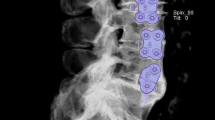

Disc morphology

Five included studies evaluated pear-shaped/irregular disc as a risk factor for cage migration and cage subsidence after LIF [38, 41, 48, 55, 56] (Fig. 3), with qualities of moderate (n = 4) and high (n = 1). For 96 cages that underwent migration or subsidence in these studies, 26 (27.1%) were inserted into a pear-shaped/irregular disc, and 165 (6.6%) were inserted into pear-shaped/irregular disc for patients without cage subsidence or migration. Regarding the incidence of combined adverse events (cage migration + cage subsidence), the third study reported eight pear-shaped discs (22.2%) at all levels with combined adverse events, and the rate dropped to 6.2% for all levels without adverse events after LIF.